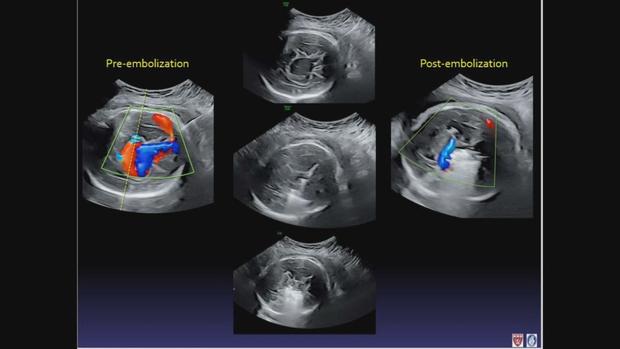

ABD'de anne karnındaki bebeğe beyin ameliyatı yapıldı

Ankara, 5 Mayıs 23 (TAK): ABD'nin Boston kentinde henüz anne karnındaki bebeğe beyin ameliyatı yapıldı.